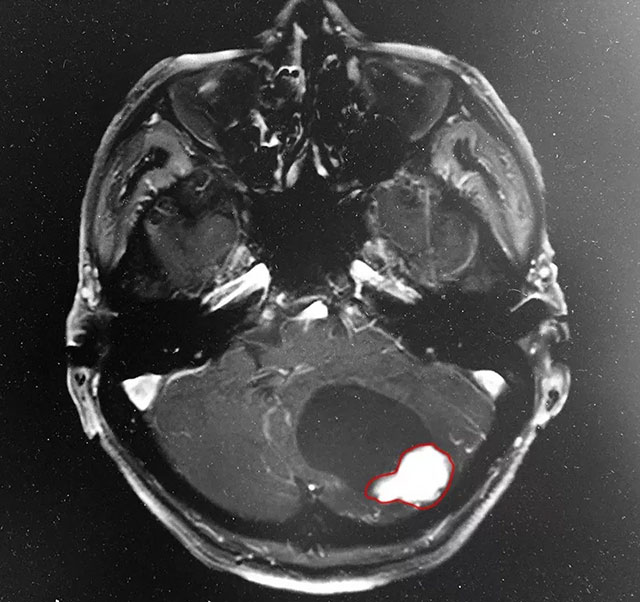

為了進一步明確病因,吳主任建議患者增強掃描:頭顱MRI平掃+增強+DWI+MRA,影像學(xué)結(jié)果提示:患者為良性的小腦腫瘤,同時結(jié)合患者病情、病癥和病史,考慮為血管母細(xì)胞瘤可能性很大。

▲ MRI影像顯示:患者為小腦腫瘤

據(jù)吳博士介紹,患者的小腦腫瘤為良性——這算是不幸中的萬幸。但他當(dāng)時的情況還是很嚴(yán)重的,由于腫瘤壓迫,腦部水腫情況比較明顯,第四腦室受壓變形,導(dǎo)水管與腦池也受壓,雙側(cè)側(cè)腦室及第三腦室明顯擴大,顱底中線結(jié)構(gòu)向左側(cè)偏移。為了患者更好的治療,吳博士特邀神經(jīng)外科特需專家李士其教授進行會診,經(jīng)過商量討論,他們一致認(rèn)為患者頭痛、惡心、走路不穩(wěn)癥狀嚴(yán)重,手術(shù)指征明顯,應(yīng)盡早手術(shù)。